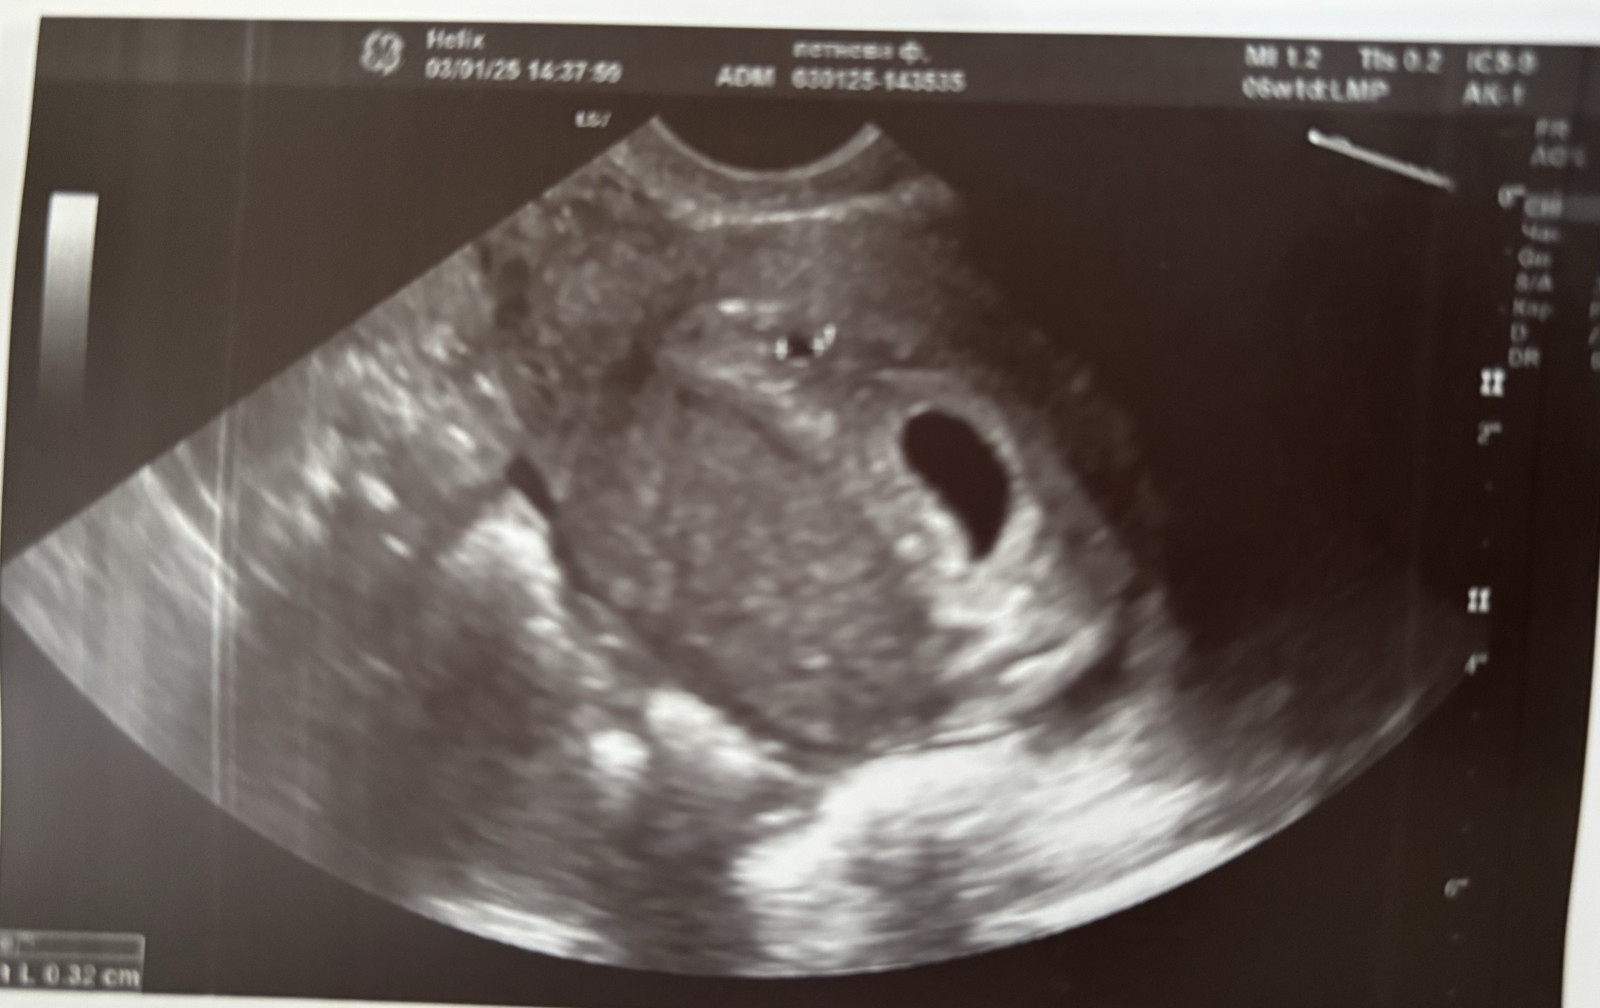

Плохое плодное яйцо